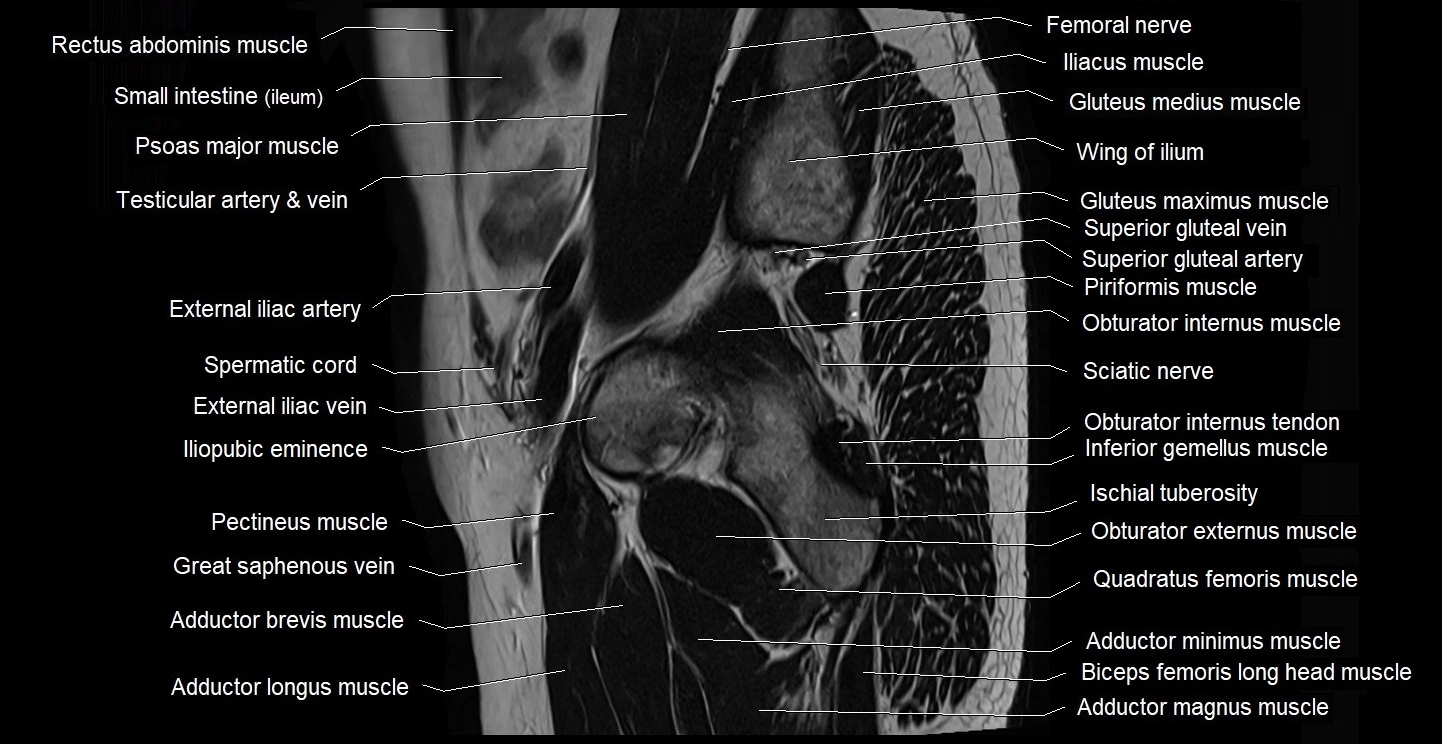

- Adductor brevis muscle

- Adductor longus muscle

- Adductor magnus muscle

- Adductor minimus muscle

- External iliac artery

- External iliac vein

- Femoral nerve

- Gluteus maximus muscle

- Gluteus medius muscle

- Gluteus minimus muscle

- Iliopubic eminence

- Inferior gemellus muscle

- Ischial tuberosity

- Obturator externus muscle

- Obturator internus muscle

- Obturator internus tendon

- Pectineus muscle

- Piriformis muscle

- Quadratus femoris muscle

- Sciatic nerve

- Spermatic cord